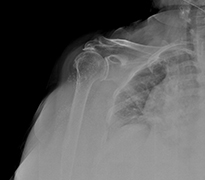

Omuz Kireçlenmesi